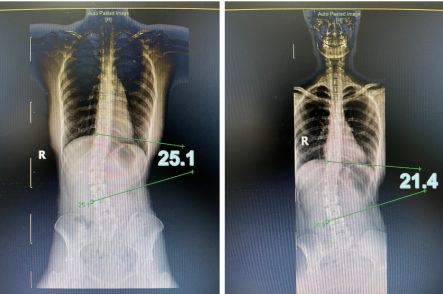

如果有明显的“高低肩”现象,建议及时到正规医院就诊。医生经过检查以及详细询问生活习惯,可以查明“高低肩”的原因并进行评估。一般情况下,需要拍摄脊柱全长片对脊柱侧弯情况进行筛查及评估。脊柱侧弯的严重程度多通过Cobb角测量,即测量脊柱侧弯两端倾斜度最大的椎体下缘垂线的交角来进行评估。

图片

康复治疗前后患者cobb角对比

康复医学科可以针对原因,对患者进行手法和运动疗法,并且进行生活、工作习惯的指导。对于轻度脊柱侧弯,一侧肩带抬高等不良姿势以及肌肉力量造成的“高低肩”,无需外科手术治疗,采用运动指导及手法治疗,可以纠正不平衡的肌肉力量,改善肌筋膜的失衡状态,往往会收到满意的效果。